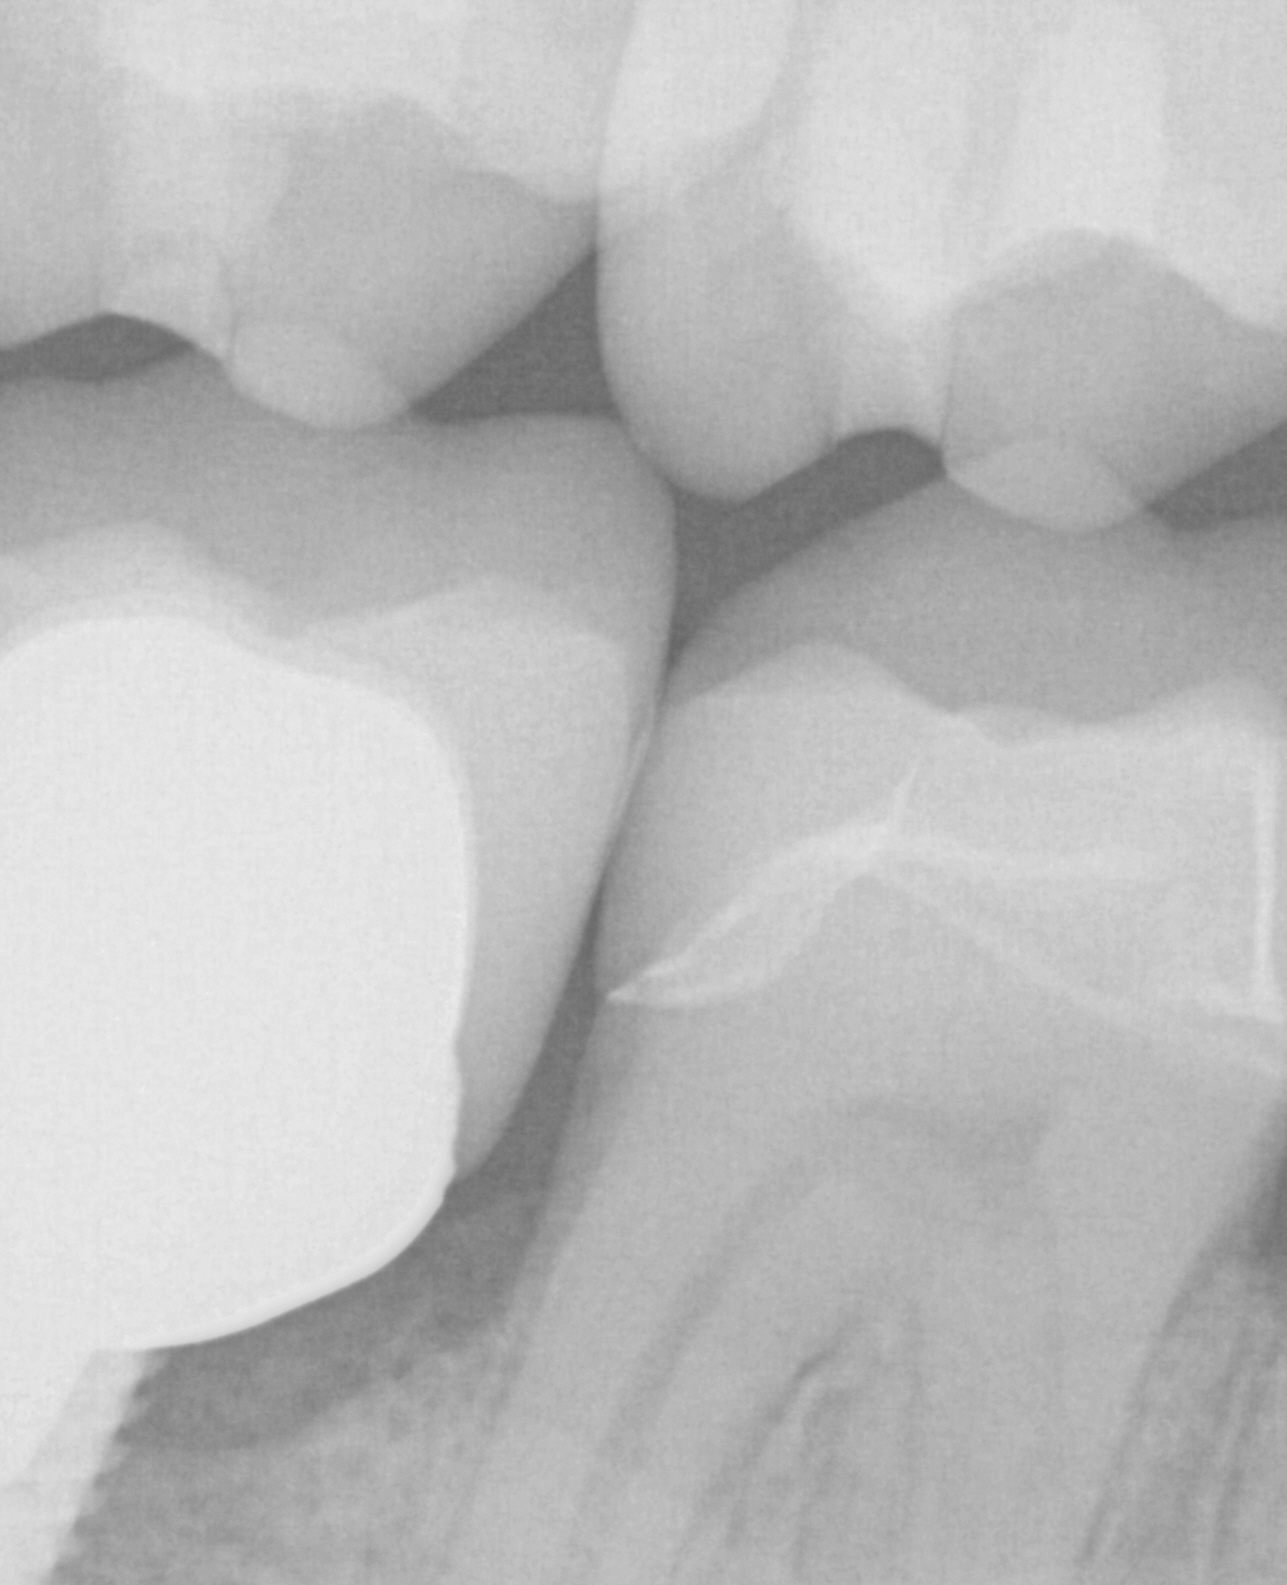

The post and core and the emax restoration were returned for delivery. The emax was not crystalized until after the abutment was cemented and then it was tried in by itself to assure proper contours and contacts. The great feature of lithium dissilicate is that you can add contact and glaze at the same time, which was required here as the mesial contact was weaker than desired after some minor adjustments

Post op x-rays to verify seat and no excess resin after flap was raised to clinically visualize that there is no excess cement